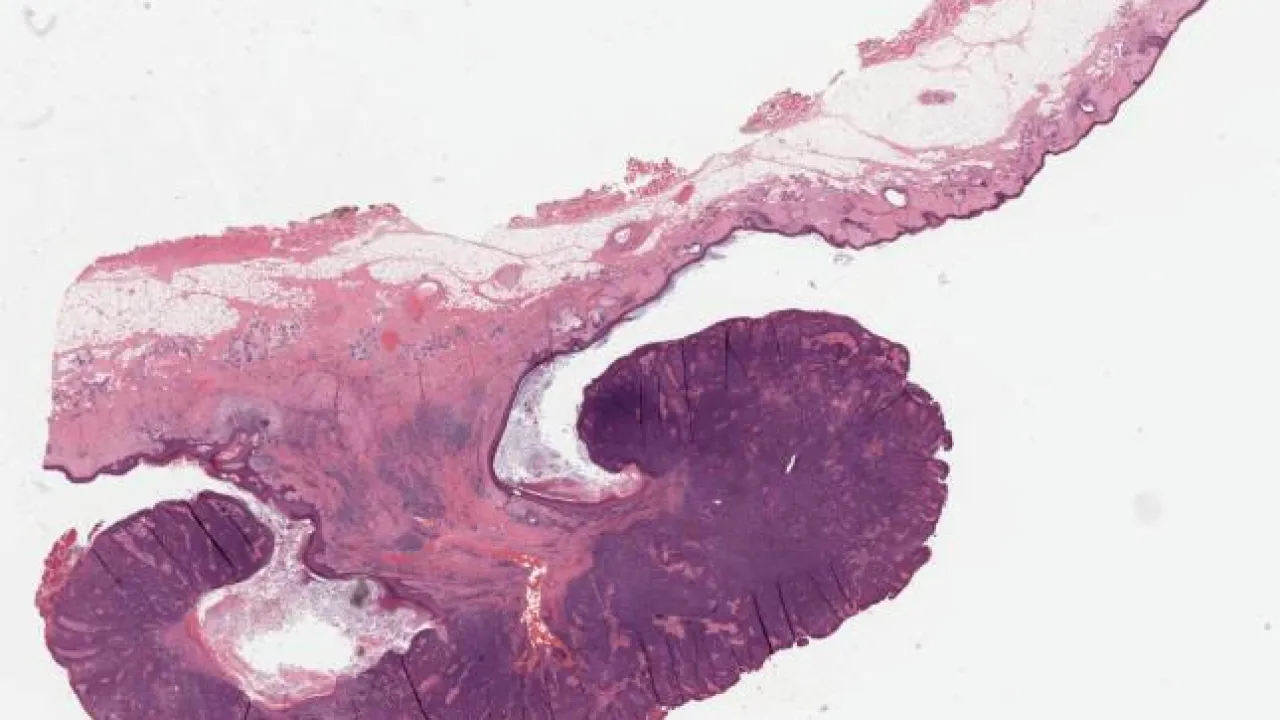

Testis, Mixed germ cell tumour